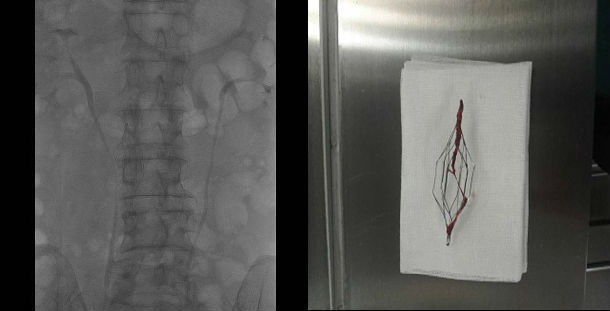

疑难性下腔静脉滤器取出的技巧及策略 - 好大夫

1129x525 - 44KB - JPEG